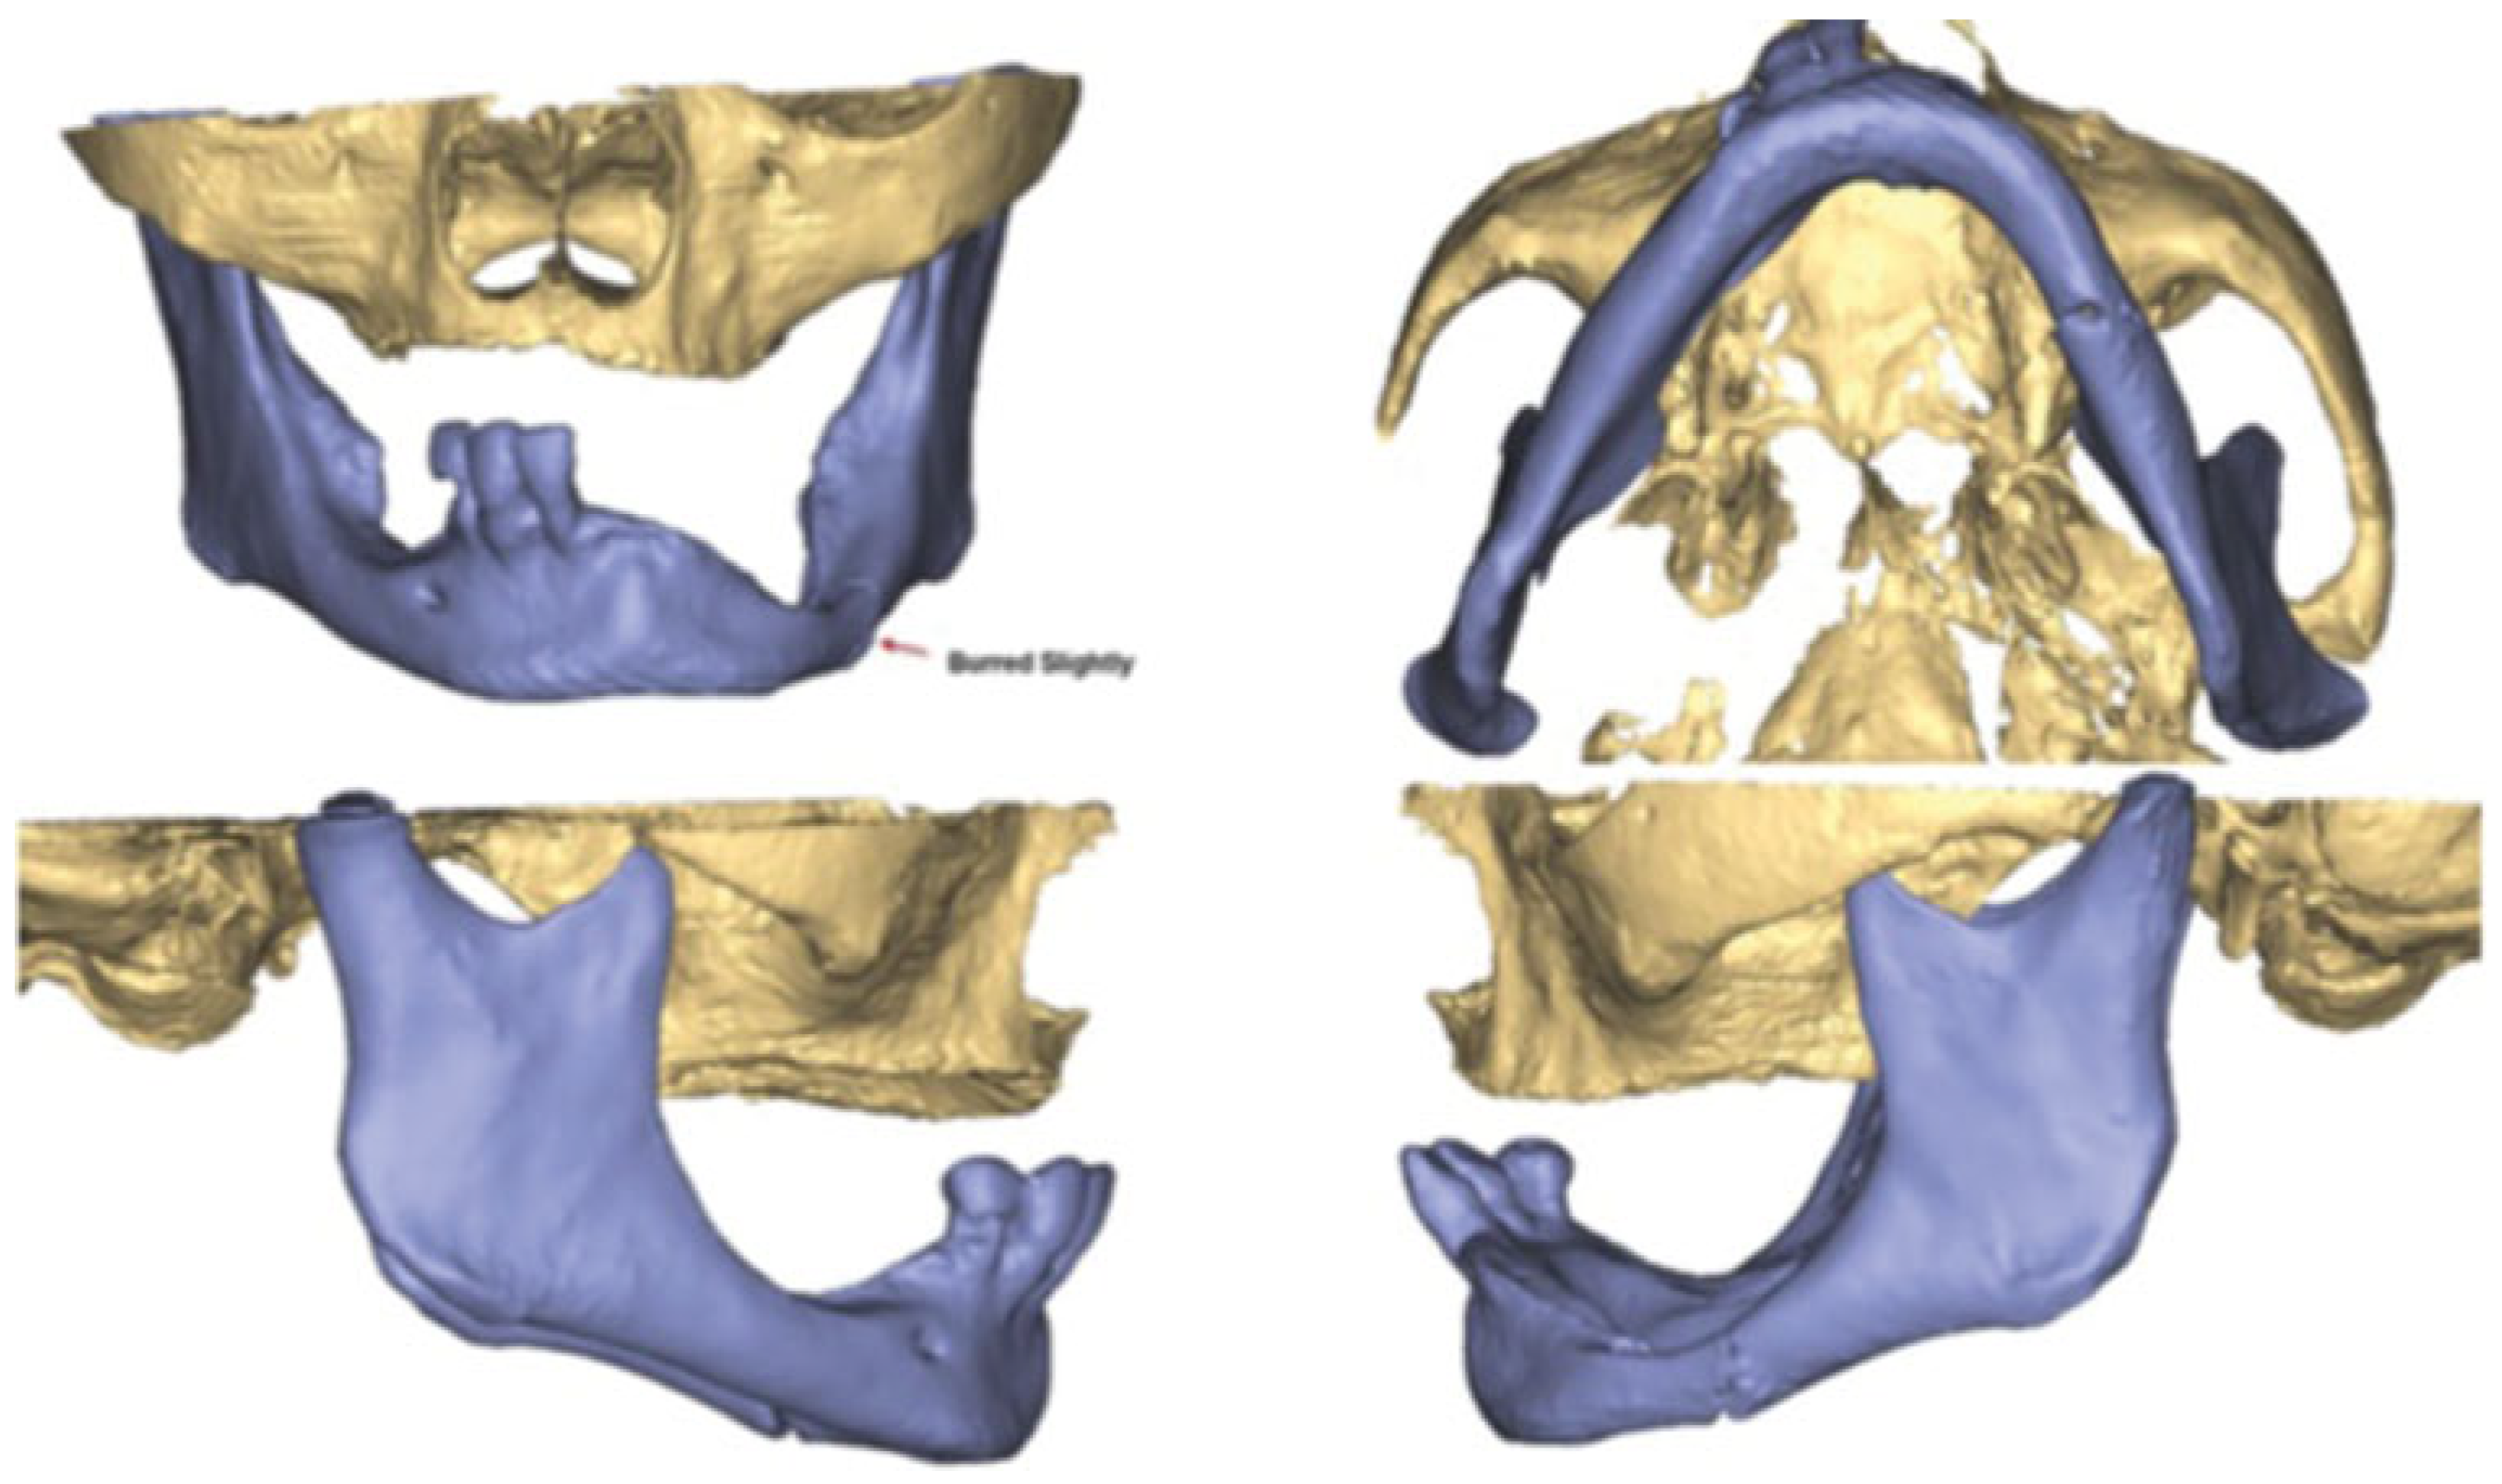

An 81-year-old woman had a fall and was diagnosed with a nondisplaced left mandible fracture. She was unsuccessfully treated with a soft diet by another oral and maxillofacial surgeon and upon repeat imaging had displacement of her fracture. She was then referred to the authors for management of her injury. Her past medical history was significant for systemiclupus erythematosus (SLE), nephritis, and a right lung mass, for which she refused workup. A CBCT was taken which showed a displaced fracture of the left mandibular body (Figure 8). VSP was again arranged using PRO PLAN. The fracture was virtually reduced and a patient-specific 2.0 mm reconstruction plate was fabricated (Figure 9, Figure 10 and Figure 11). The patient was taken to operating room and a submandibular approach was used for exposure of the left mandible. The reconstruction plate was applied after reduction and debridement of the fracture site and secured with bicortical locking screws (Figure 12). The incision was closed in layered fashion. The patient was discharged home the same day. A postoperative panoramic radiograph showed adequate reduction of the fracture (Figure 13). She went on to heal well without complication and was last seen at 6 months postsurgery.

Figure 9. PROPLAN 3-day reconstruction of mandible fracture.

Figure 10. PROPLAN 3-day reconstruction after reduction of fracture.

Figure 11. Virtual surgical planning of patient-specific reconstruction plate.